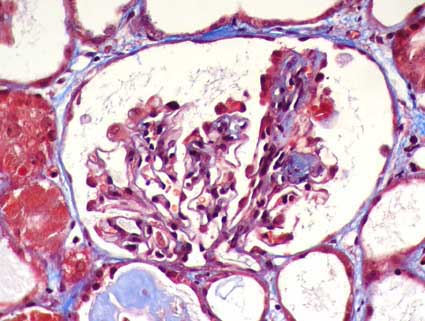

Figura 1.

Colapso de capilares glomerulares y aspecto "solidificado" del

mismo. H&E, X400.

Figura 3.

La hipertrofia e hiperplasia de podocitos es un elemento muy importante

y característico en esta enfermedad. Tricrómico de Masson,

X400.

Figura 4.

Las lesiones colapsantes pueden ser segmentarias (como en la imagen) o

globales. Tricrómico de Masson, X400.